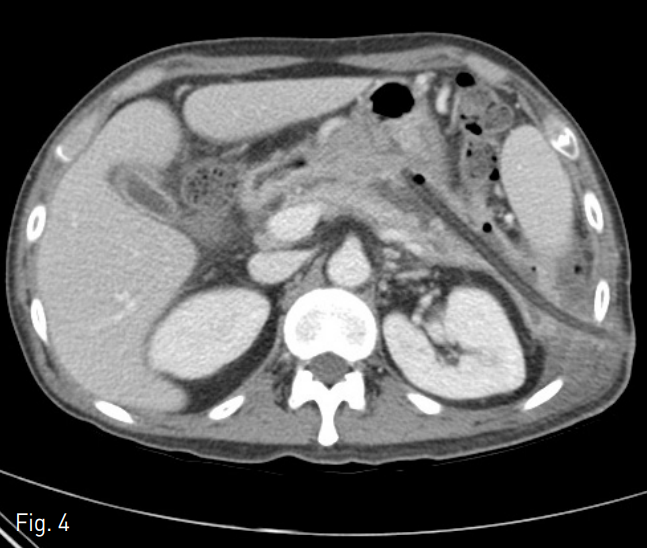

Fig. 4

Contrast-enhanced axial CT scan on 2 months after initial CT scan shows markedly decreased extent of previous walled-off necrosis, remaining small amount of fluid collection along the drainage catheter at left anterior pararenal space.